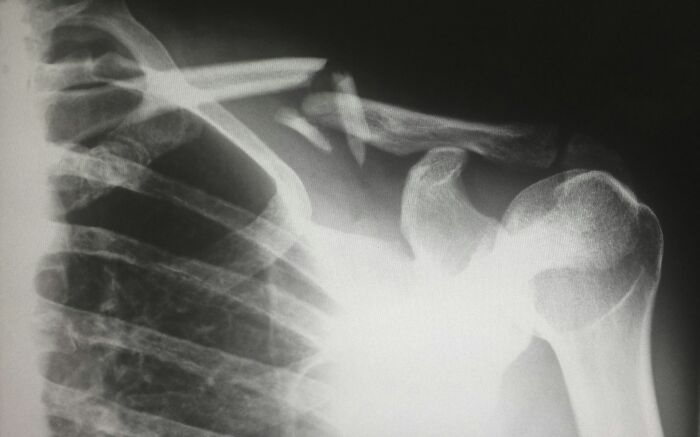

I worked at a company that made X-Ray machines. Doctors who didn't want to change the developer chemicals at the regularly scheduled times (to save money) would just crank up the rads when they X-Rayed patients.